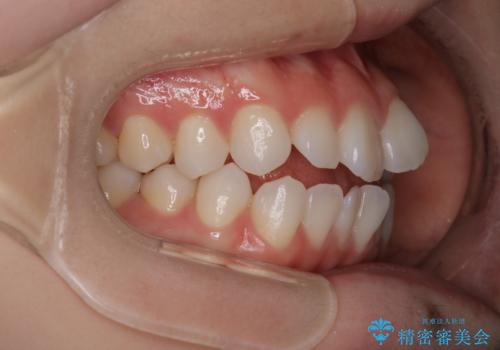

【審美装置】前歯で噛めない!抜歯しないで治したい

- 前歯の捻転とかみ合わせを主訴に来院されました。今回は抜歯をせずにIPRを実施し、並べる計画を立てました。

ワイヤー矯正を行いながら、顎間ゴムを患者さまにご協力していただき、短い期間で終了できました。